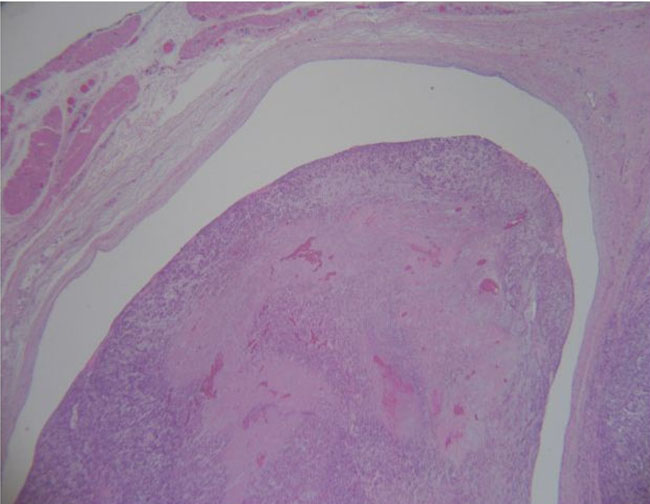

The patient underwent right radical inguinal orchiectomy with excision of the spermatic cord. A paratesticular mass grossly measuring 9.7 × 7 × 6.5 cm was excised and sent for pathologic examination. Microscopy revealed a malignant spindle cell neoplasm consistent with leiomyosarcoma associated with areas of hypercellularity measuring 24 mitoses per 10 high-power fields (0.1735 mm2) and positive surgical margins (Figure 2). There was evidence of lymphovascular involvement of the testicular vein without invasion of the vas deferens or the spermatic cord stroma (Figure 3 and Figure 4). Immunohistochemistry was diffusely reactive for calponin, caldesmon, desmin, and smooth muscle actin immunostains. The final pathologic stage classification was pT2 (pTNM; American Joint Committee on Cancer, 8th edition). Staging CT scans of the chest, abdomen, and pelvis were negative for metastatic disease. Following multidisciplinary discussion, adjuvant radiotherapy was offered but deferred after careful consideration of this patient’s case. Scrotal immobilization during radiotherapy is challenging and limits the delivery of a targeted, reproducible radiotherapy dose. Furthermore, an extensive postoperative radiotherapy field would be required. The patient remains disease-free at one month of follow-up after surgery, with plans for continued surveillance.

Figure 3: H&E stain, 400× demonstrating leiomyosarcoma attached to the wall of the spermatic vein.

Figure 4: H&E stain, 200× demonstrating paratesticular leiomyosarcoma inside lumen of testicular vein.